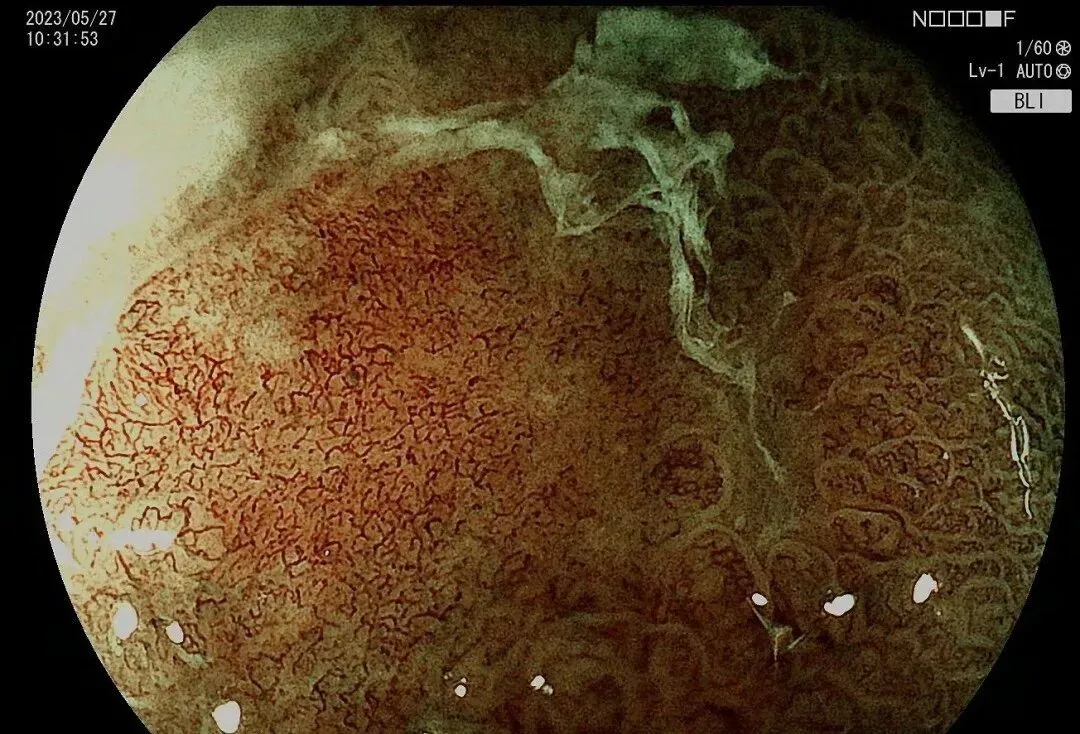

这张图清晰地展示了慢性萎缩性胃炎到胃癌的发展过程。从正常胃黏膜到癌前病变,再到早期胃癌、进展期胃癌,这个过程可能需要几年甚至十几年的时间。如果我们能在这个过程中通过筛查及时发现,就能将胃癌扼杀在摇篮里。